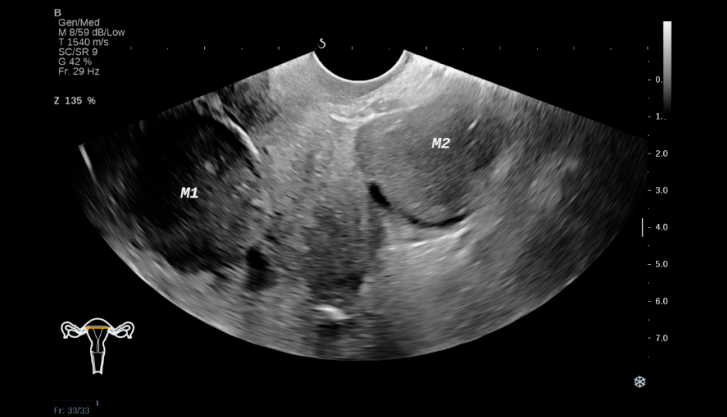

1、动态卵泡监测

传统的卵泡监测方法往往只是在特定时间点进行简单的超声检查,获取的信息较为有限。而HRC专家采用的动态卵泡监测技术,通过在整个月经周期内多次、持续地进行超声检查,能够实时、全面地追踪卵泡的生长、发育、成熟以及排卵情况。这不仅可以准确掌握女性的排卵时间,为后续的取卵手术提供理想时机,还能通过观察卵泡的形态、大小变化以及生长速度等指标,评估卵子的质量和卵巢的储备功能。例如,如果发现卵泡生长缓慢、形态不规则或数量过少时,HRC专家就会据此调整治疗方案,提前采取相应的干预措施。